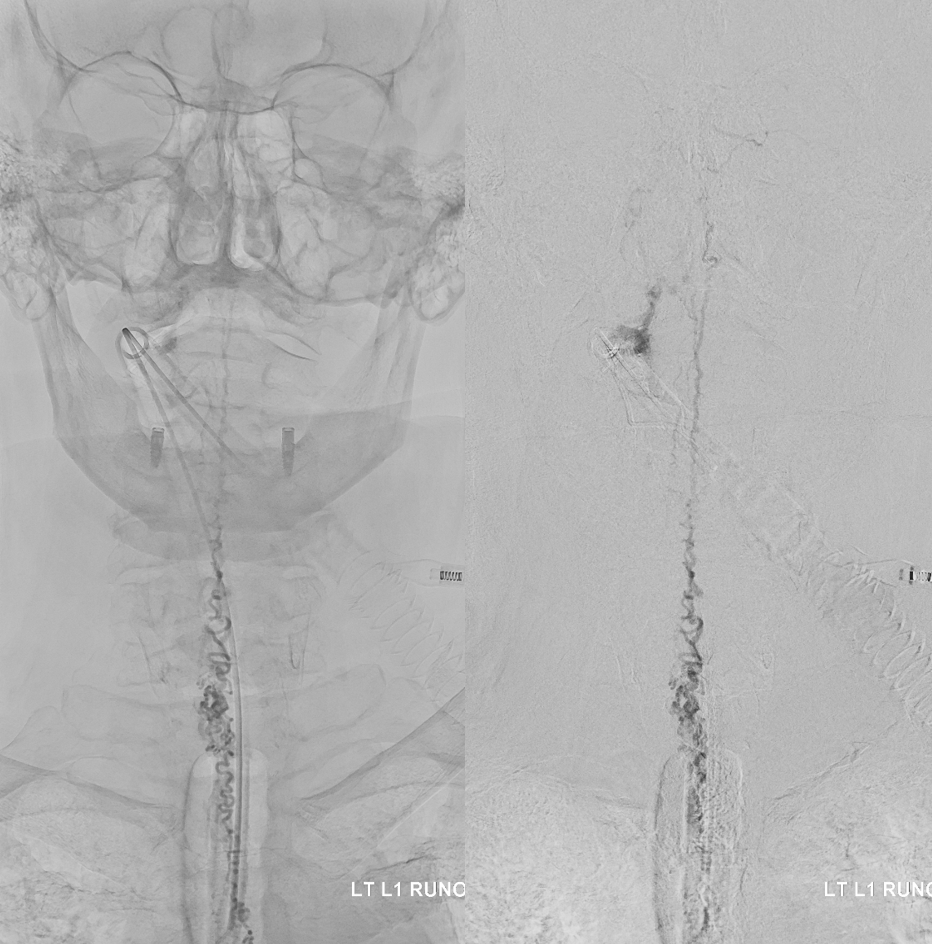

Fistula at left L1

All dural fistula pathophysiology, and spinal too, consists of two key factors. One is fistula. The other is degree of venous congestion. Normal spinal venous anatomy consists of multiple radicular veins which drain the cord via nerve root sleeve / foramen into the epidural venous plexus. These veins are almost always deficient (missing from getgo, thrombosed, both?) in patients with spinal dural fistulas. Could it be that venous deficiency comes first, and fistula emerges later? Probably not, but interesting to consider. In any case, good spinal angiography involves imaging of fistula runoff to see extent of congestion and where drainage finally happens. In this case, there are no radicular veins in lumbar or thoracic cord at all. Not until the foramen magnum/C1/C2 do we see any outflow, and that is insufficient as well — with congestion extending all the way up to basal vein! Note perfect visualization of anterior pontomesencephalic and interpeduncular veins. When it finally reaches basal vein, the outflow is diluted by cranial venous tributaries.

More info on radicular veins can be found in Spinal Venous Anatomy Page

In retrospect, corresponding veins on MRI and angio